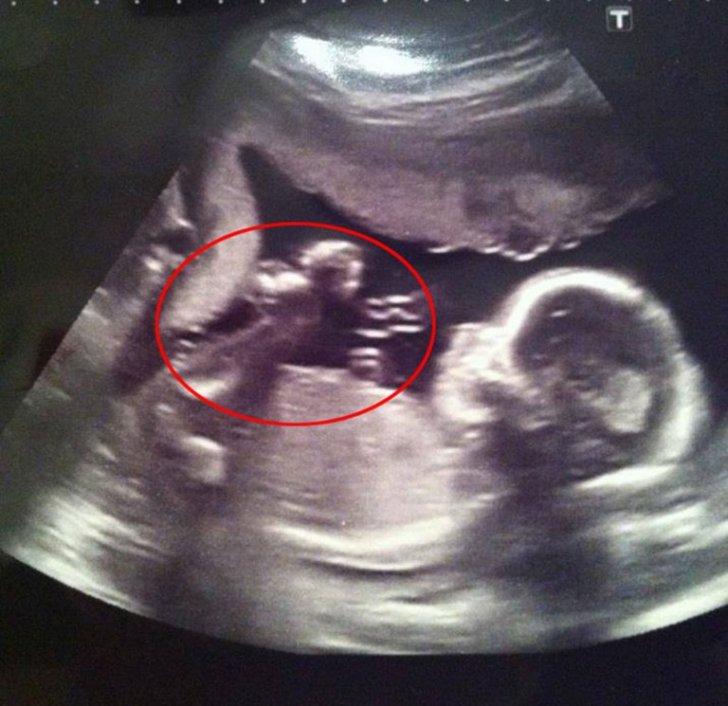

Când medicul a pronunțat rezultatul, ecograful a arătat clar cinci feți! Nașterea unor cvintupleți fără fertilizare in vitro este un fenomen foarte rar: 1 caz la 55 de milioane. Și în timp ce Oksana încerca să accepte noutatea, medicii discutau entuziasmați despre pacienta lor unică. Majoritatea colegilor lor nu vor vedea așa ceva în întreaga lor viață!